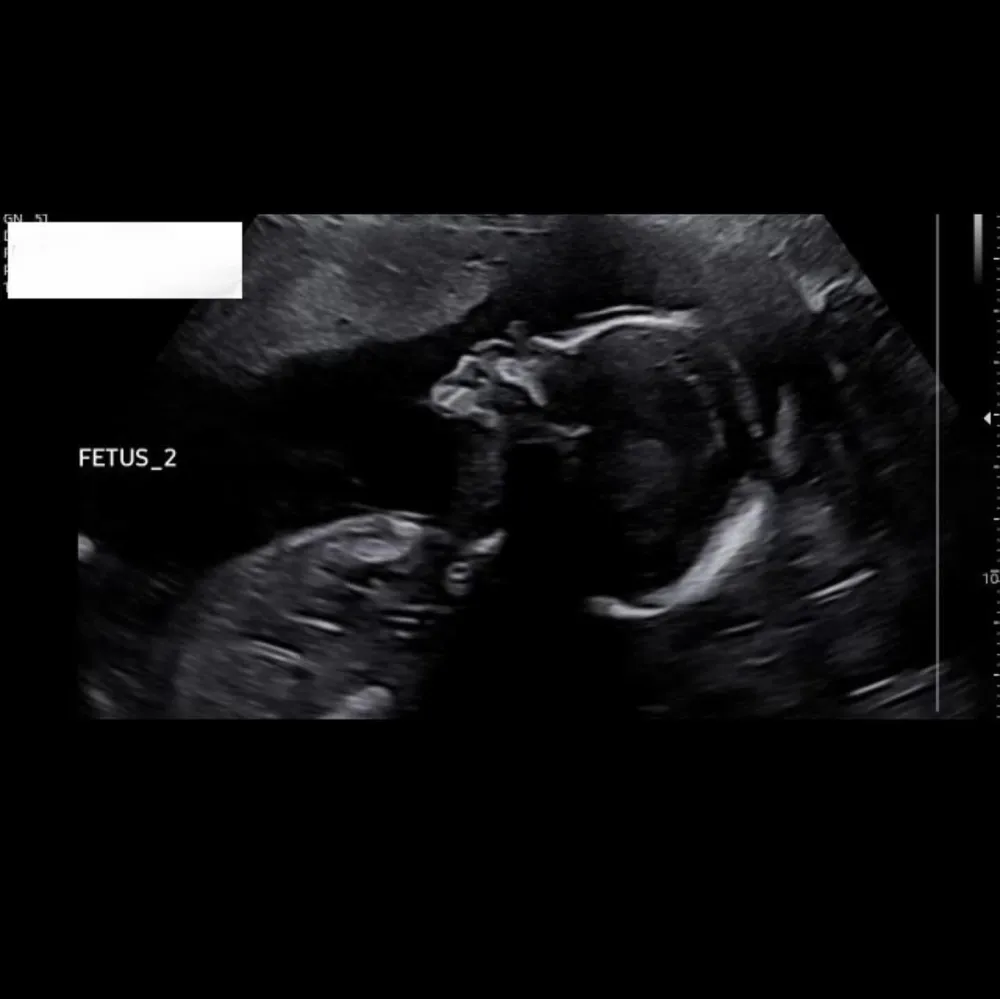

“Evolution of the twin bump 🤍,” Lowry, 31, wrote via Instagram on Tuesday, December 5, sharing photos of her stomach and ultrasound footage of the twins. “Watch the transition from baby A to baby B in the video 🥹.”

Last month, Lowry opened up about feeling anxious due to her “high-risk” pregnancy. “We are just leaving the 20-week anatomy scan for the twins and I cried coming out,” she said in a TikTok video. “Just because the doctor came in to say that everything was fine, they looked great, and it was just a relief.”